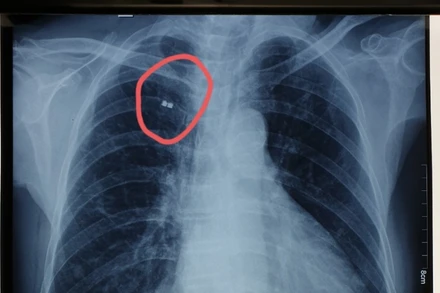

Vị trí mảnh bom trước khi gắp ra. (Ảnh: BVCC)

Ngày 25-3, Bệnh viện Xuyên Á Tây Ninh thông tin, vừa gắp ra từ lồng ngực một cựu chiến binh một… mảnh bom. Người bệnh là ông P.V.N. (71 tuổi, huyện Bến Cầu, Tây Ninh) từng bị mảnh bom găm vào thành ngực bên phải từ năm 1972. Tuy may mắn thoát chết nhưng người thương binh này phải sống chung với vật thể lạ trong 50 năm qua.